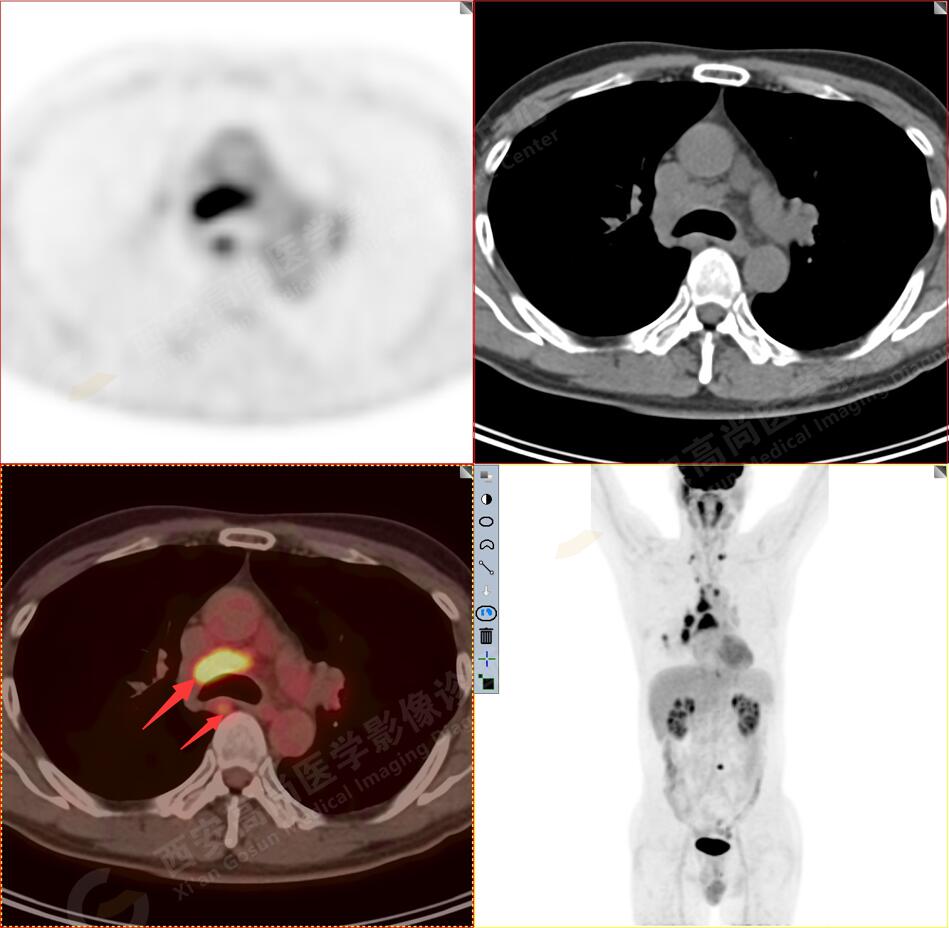

2.以下為全身多發(fā)轉(zhuǎn)移灶

3.右側(cè)肺門、縱隔(1L、1R、3A、4、6、7組)及雙側(cè)鎖骨上多發(fā)腫大淋巴結(jié),呈不同程度FDG代謝異常增高,考慮為淋巴結(jié)轉(zhuǎn)移。

4.右后胸膜輕度增厚,形成多個(gè)條狀軟組織病變,呈FDG代謝輕度異常增高,考慮為轉(zhuǎn)移性病變;右側(cè)胸腔微量積液。